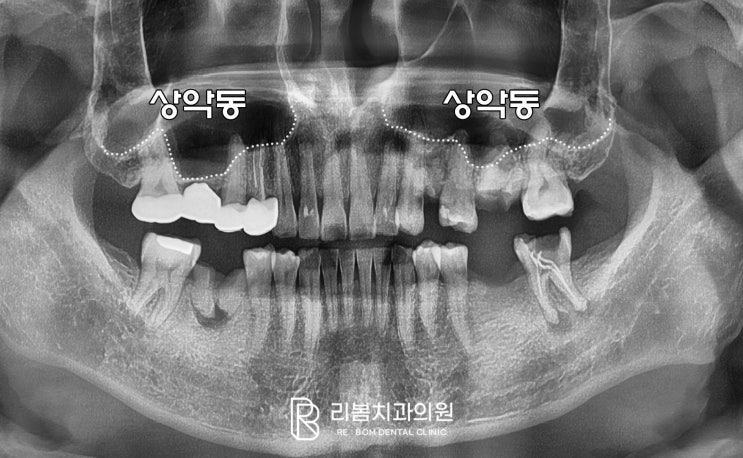

송도 치과 임플란트 상악동 거상술, 2가지 방법에 대하여(치조정 & 측방 접근법)

송도 치과 리봄의 박현호 원장입니다. 임플란트를 심을 때는 남아있는 잇몸뼈의 양과 두께가 얼마나 되는지...